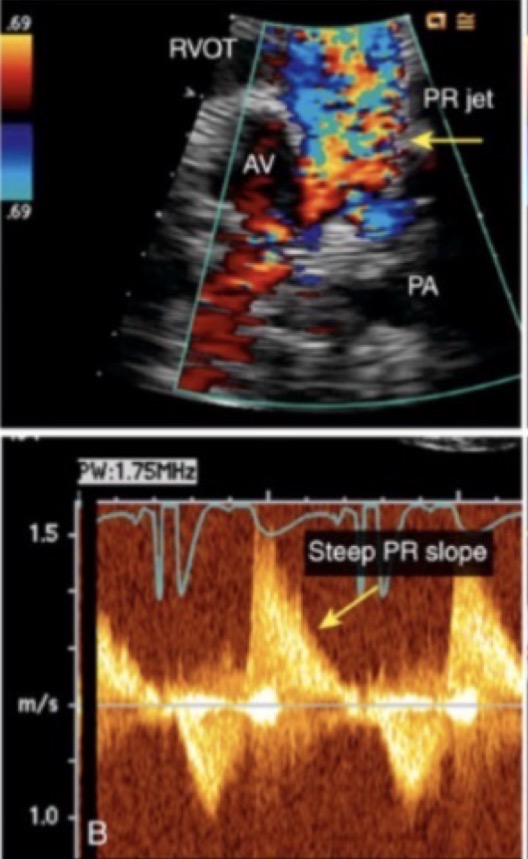

Full opening and closing

What is M-Mode looking for when evaluating the mitral valve

If the MV appears abnormal, prosthetic, or has been repaired

When should you measure PHT if there is stenosis in the MV